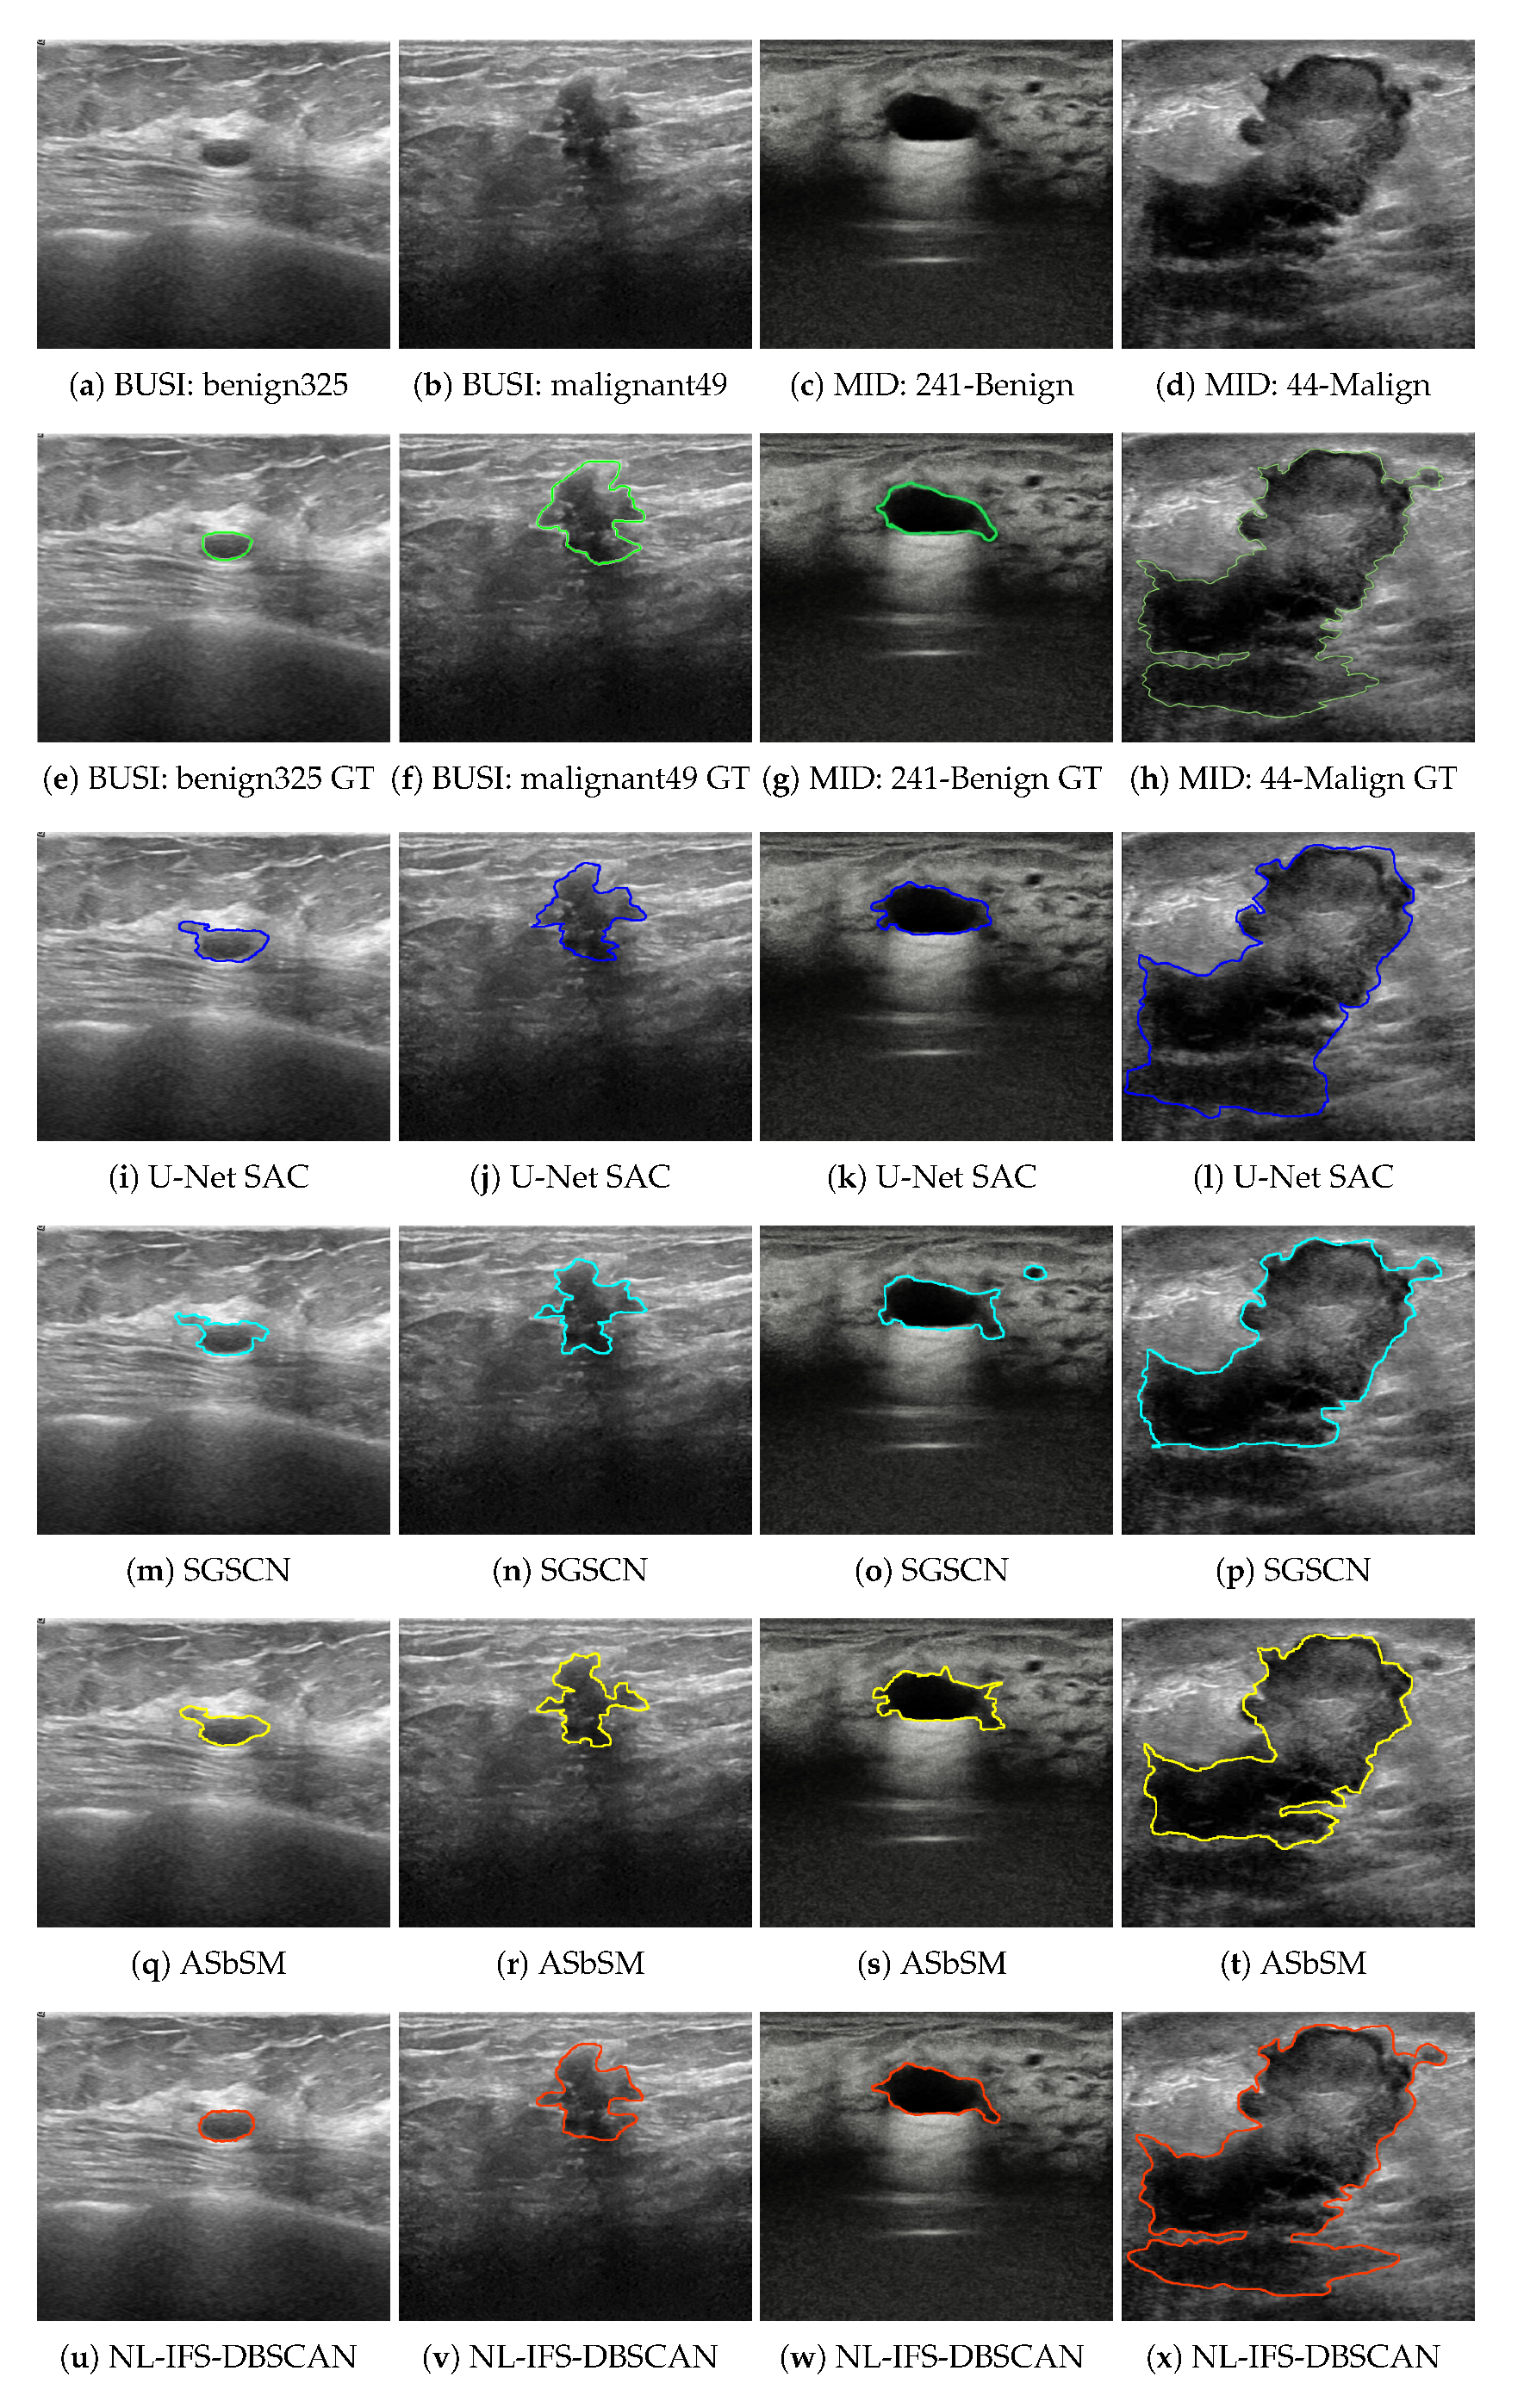

4.2. Experiment 1: BUSI Dataset

4.3. Experiment 2: MID Dataset